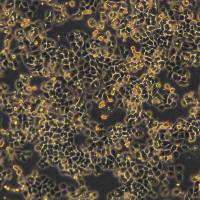

细胞名称:3dGRO® Pancreatic Organoids (OCIP.335)

特点和优势:Cryopreserved patient derived pancreatic cancer organoids (PDOs)

类器官分化流程。人结肠类器官可以通过定形内胚层、后肠内胚层和结肠类器官扩增阶段,使用三步分化方案从人 iPS 细胞生成。 SCM302:定形内胚层诱导培养基,SCM303:后肠诱导培养基,SCM304:3dGRO™ 人结肠类器官扩增培养基 类器官培养方案 步骤1:人 iPS 细胞分化为定形内胚层(第 0-4 天) 注意:起始材料为高品质未分化的人 ES/iPS 细胞(SCC271)(细胞融合度约为 70-80%,且含有 准备单细胞传代培养基。将 ROCK 抑制剂 (ROCKi) Y

在自然界,许多动物拥有着令人惊叹的再生能力,比如「超级选手」海星、蝾螈、斑马鱼(心脏可再生)、扁虫(头部可再生)……科学家们一直希望将这些神奇应用于生命科学,解决器官移植、药物开发等问题。干细胞是组织再生的「源泉」,在此基础之上诞生的「类器官」(organoids)给予了更多的可能。这些在体外培养的微小结构,可以模拟人体器官的复杂结构,还可以重塑体内肿瘤组织的关键特性,有着代替动物试验、实现器官移植的巨大潜力。类器官的获得与治疗潜能01 助力精准医学的「秘密武器」自 2000 年代末,生物